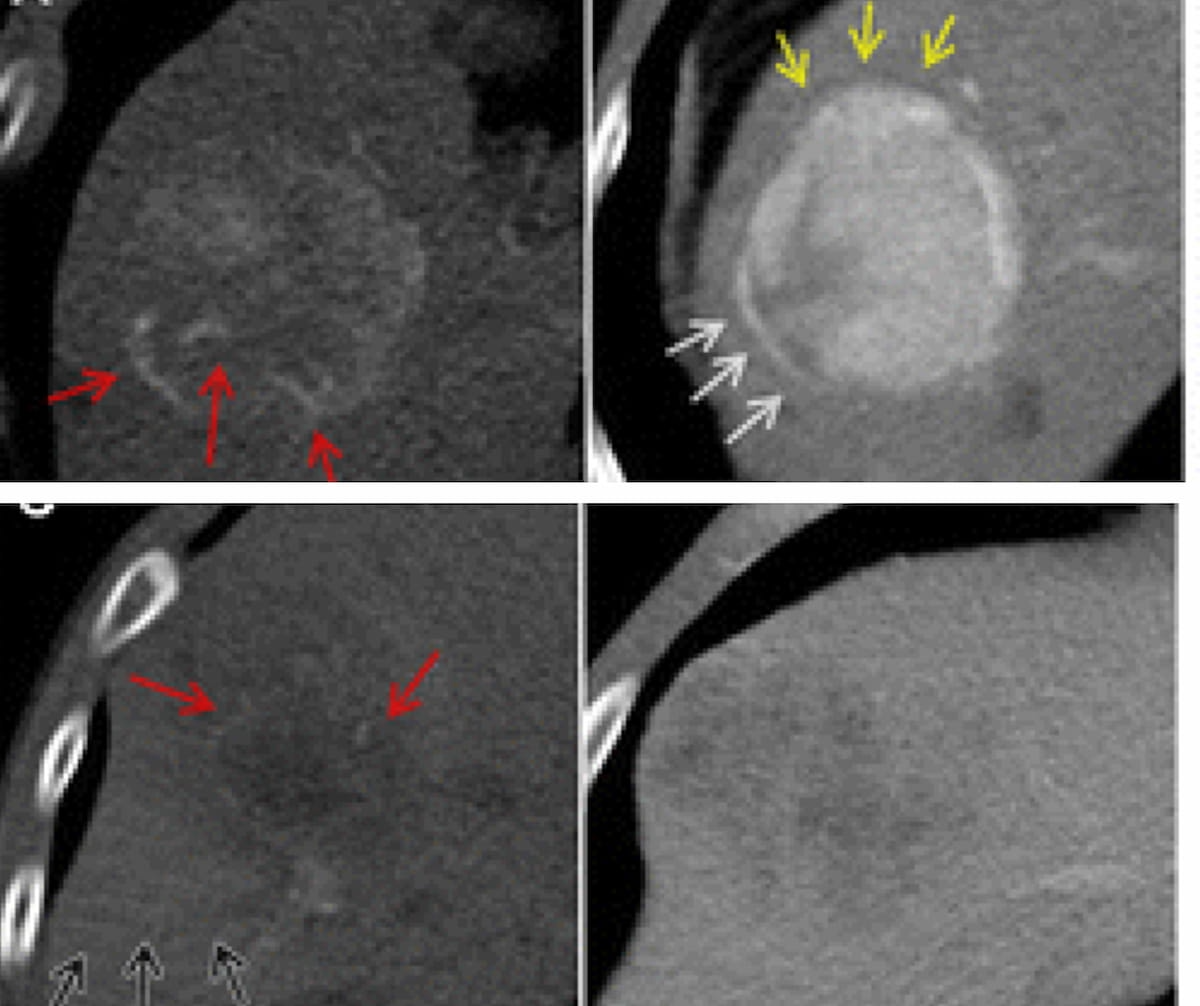

Исследователи обнаружили, что комбинация признаков гибридной модели, включая двухпризнаковый предиктор венозной инвазии (TTPVI), псевдокапсулу, показатель радиомики и перитуморальное усиление, имеет площадь под кривой (AUC) от 84 до 86 процентов для предсказания MVI в больных ГЦК. Четыре вышеупомянутых признака были независимо связаны с MVI с многопараметрическим анализом, показывающим отношение шансов (ОШ) 6,78 для TTPVI, 4,50 OR для псевдокапсулы, 3,20 OR для перитуморального усиления и 2,23 OR для оценки радиомики.

Новое исследование предполагает, что новая радиомика модель, которая может прогнозировать микрососудистую инвазию (МВВ) на основе многофазной компьютерной томографии (КТ), может быть полезной в предоперационном планировании для пациентов с гепатоцеллюлярной карциномой (ГЦК), подвергающихся процедуре гепатэктомии.

Для исследования, недавно опубликованного в журнале Radiology , исследователи разработали гибридную многофазную модель радиомики CT для прогнозирования MVI, а также стремились идентифицировать дифференциально экспрессируемые гены, связанные с MVI у пациентов с ГЦР. Согласно исследованию, когорта исследования состояла из 773 пациентов (средний возраст 56 лет), включая 586 пациентов с вирусной инфекцией гепатита В (76 процентов) и 481 пациента с циррозом печени (65 процентов).